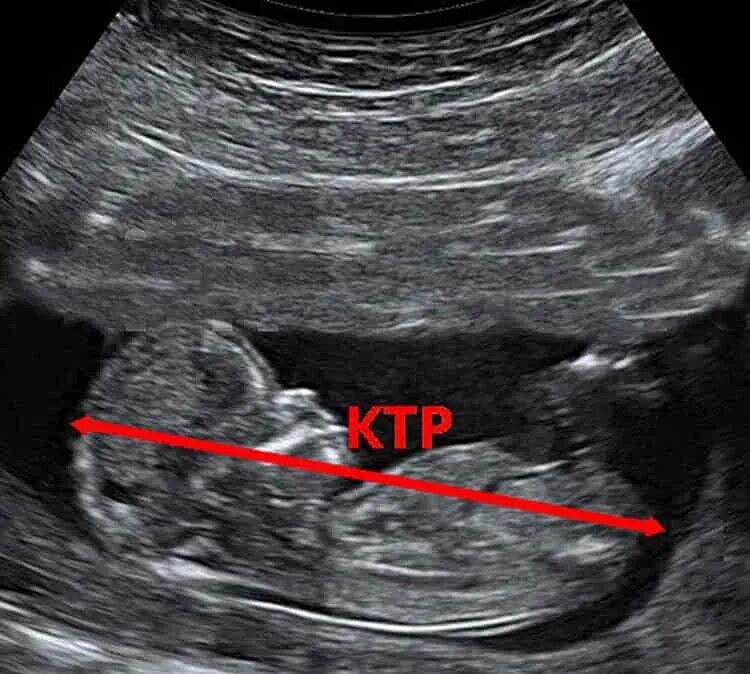

7 12 недель